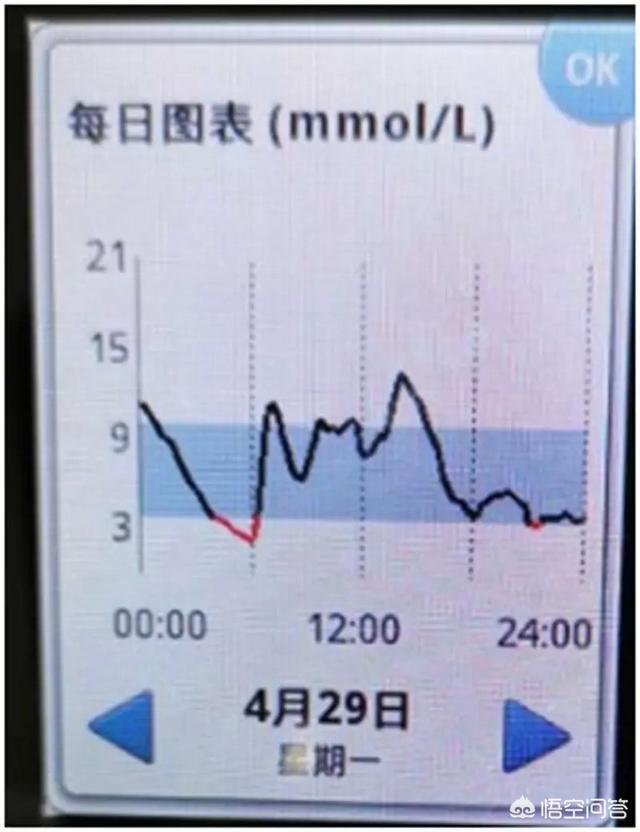

以下は、血糖値の低下が速すぎる、ダイナミック・グルコース・メーターを装着した糖質患者のグルコース・グラフである:

この患者の血糖値は午前0時から午前6時まで "滝のように "下がり続け、その結果、午前4時から午前6時まで低血糖が持続した。